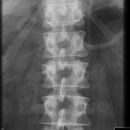

BWK 5 Fraktur